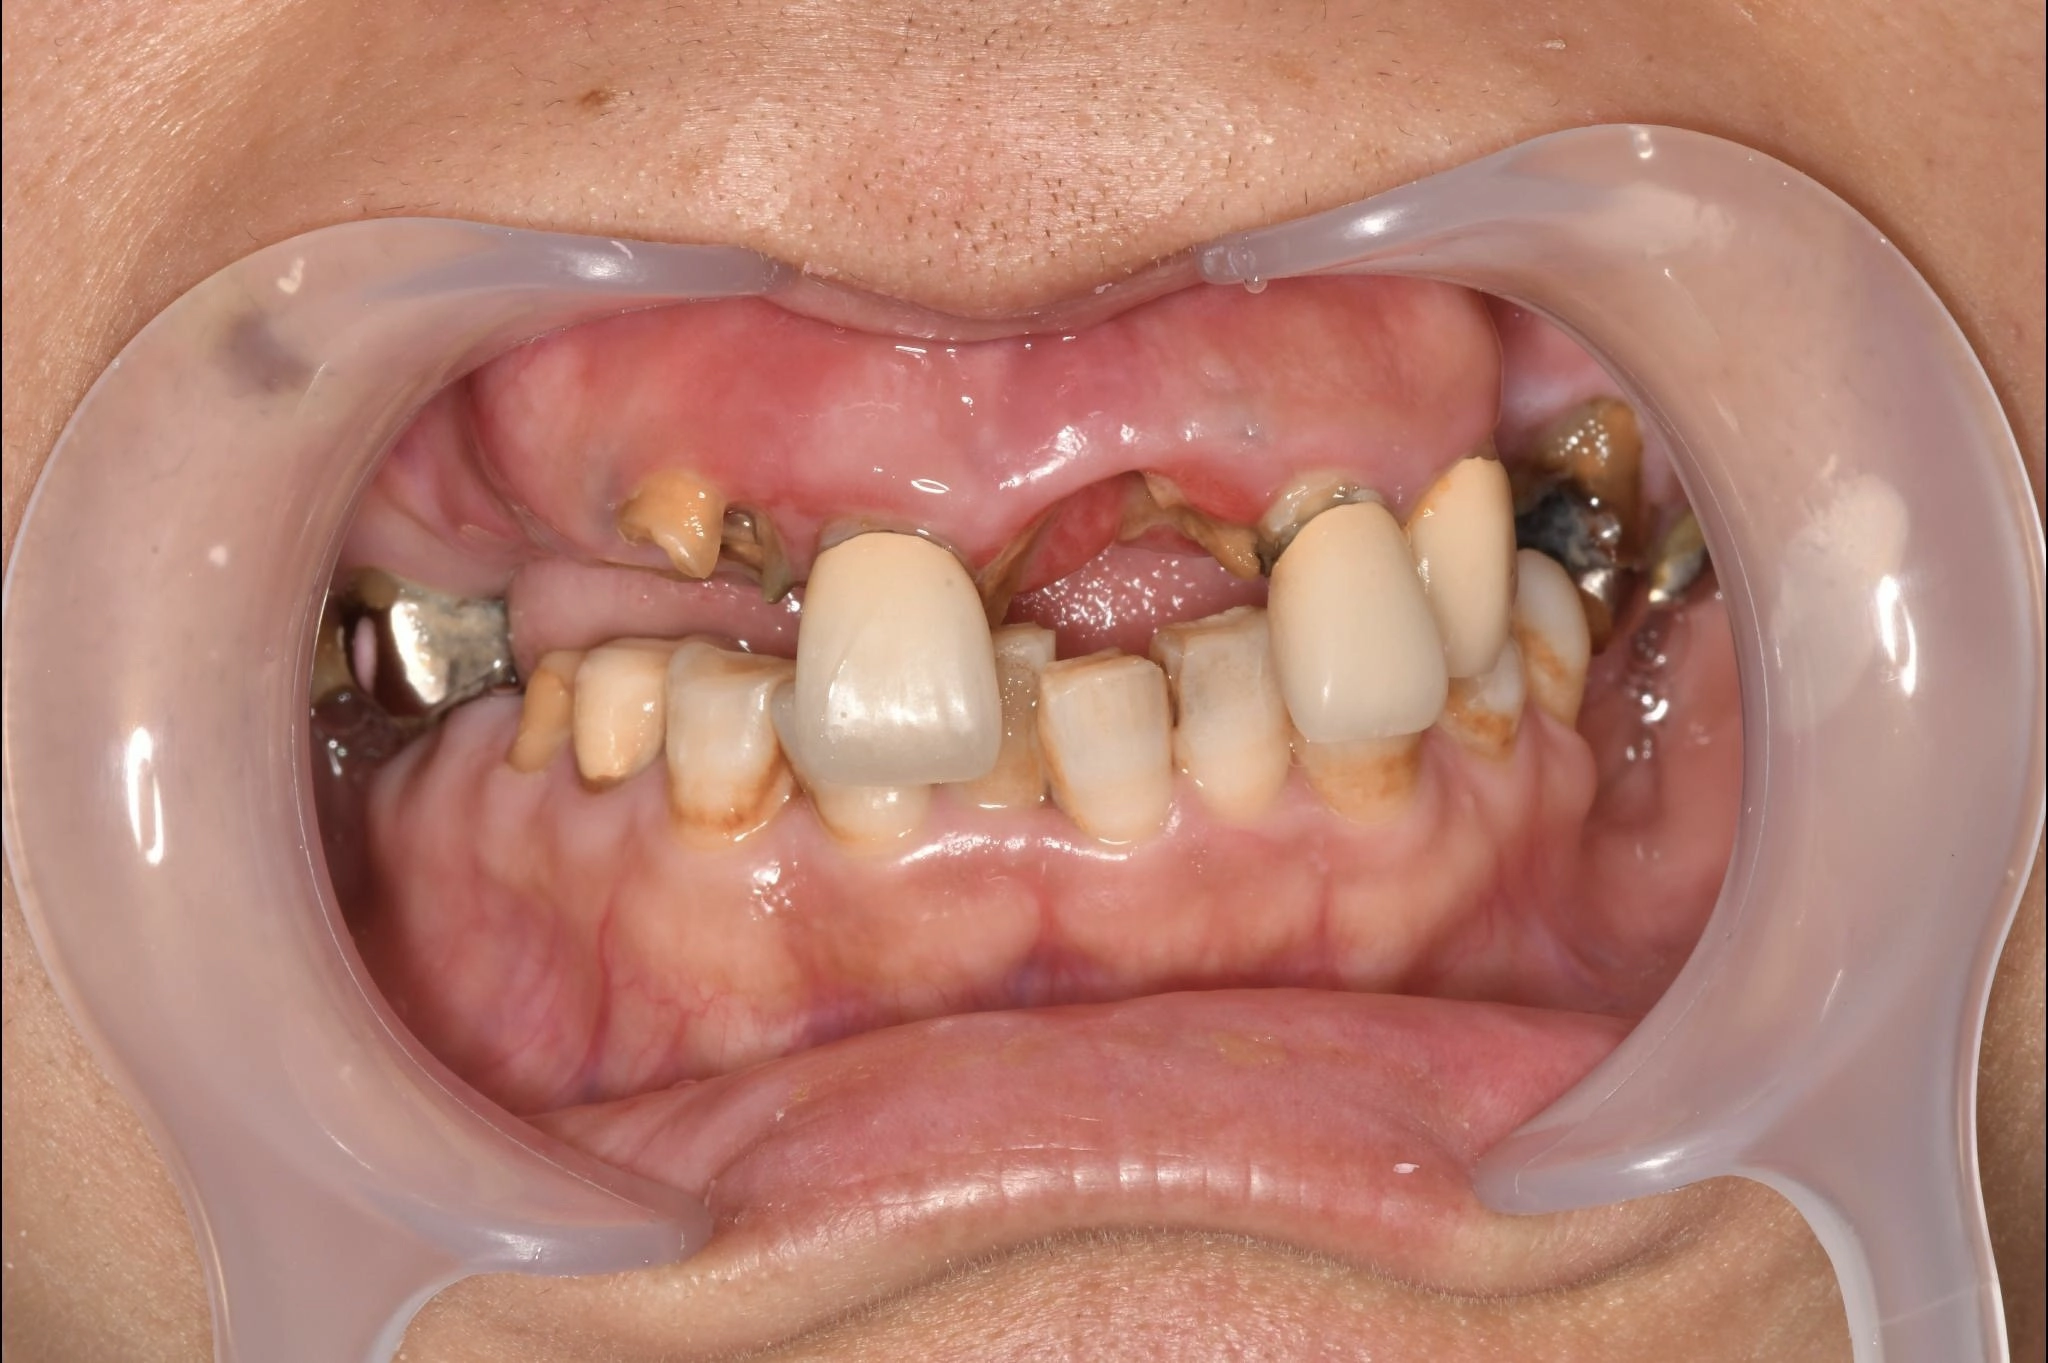

福岡県 46歳(女性)

「根本的な改善をしたい

内容 :上下顎オールオン4ザイゴマ0

費用 :4,822,400円

※モニター価格

期間 :半年

リスク:出血・腫れ・痺れ・痛み

他院で治療を行なっていましたが、根本的な改善には至らないまま不安な状態が続いていました。

カウンセリングで治療の流れや方法について詳しく説明を聞いて手術することを決意しました。

手術前は恐さがあり、緊張していましたが、想像していたような痛みはなく、うたた寝しているような感じでした。気づけば終わっていて、とても満足しています。

元々の自分の歯と比べると仮歯が入った段階でも綺麗になっていて嬉しかったです。この治療法を選んで良かったと思います。